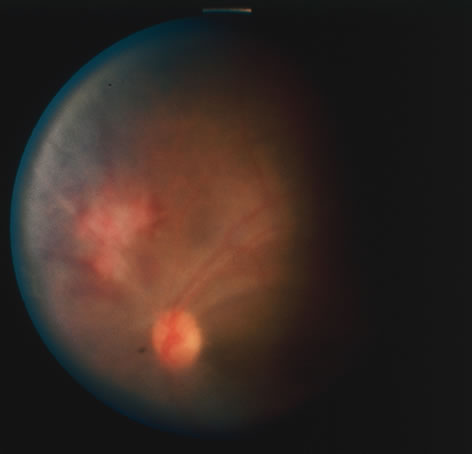

In primary ocular HSV infections, a severe follicular conjunctivitis with regional adenopathy is present. Vesicles may appear on the eyelid skin or lid margin, producing blepharitis (Fig. 3). Corneal involvement initially takes the form of a superficial punctate keratitis, which may progress to dendritic or geographic ulceration. Stromal infiltrates and uveitis are less common and relatively mild in primary disease. In uncomplicated cases, lesions usually heal completely in 2 to 3 weeks without scarring. Most cases of ocular HSV are recurrences. Recrudescent ocular herpes may take the form of dendritic or geographic ulcers, recurrent erosions, interstitial or disciform stromal keratitis, and anterior uveitis.3 HSV may also be an agent of retinitis and acute retinal necrosis (Fig. 4).

The acute retinal necrosis (ARN) syndrome is most often caused by the herpes zoster virus, although occasionally it may be a result of herpes simplex infection.12 It is typically described in healthy patients although association with immunosuppressed patients has also been described. Granular, nonhemorrhagic areas of retinal necrosis may be observed in the fundus, often rapidly coalescing with resulting blindness often caused by retinal detachment. There is often an associated vasculitis and vitritis. In immunocompromised patients VZV or HSV retinitis may also take the pattern of progressive outer retinal necrosis (PORN) (Fig. 6). PORN differs from ARN in that the former is multifocal, localized to the outer retina, and is less often associated with vasculitis and vitritis.